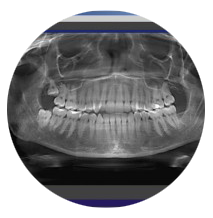

La lastra panoramica (ortopantomografia) che visualizza tutta la bocca e dà un quadro generale. Sebbene non sempre indispensabile, è consigliabile effettuarne una ogni qualche anno di controllo.